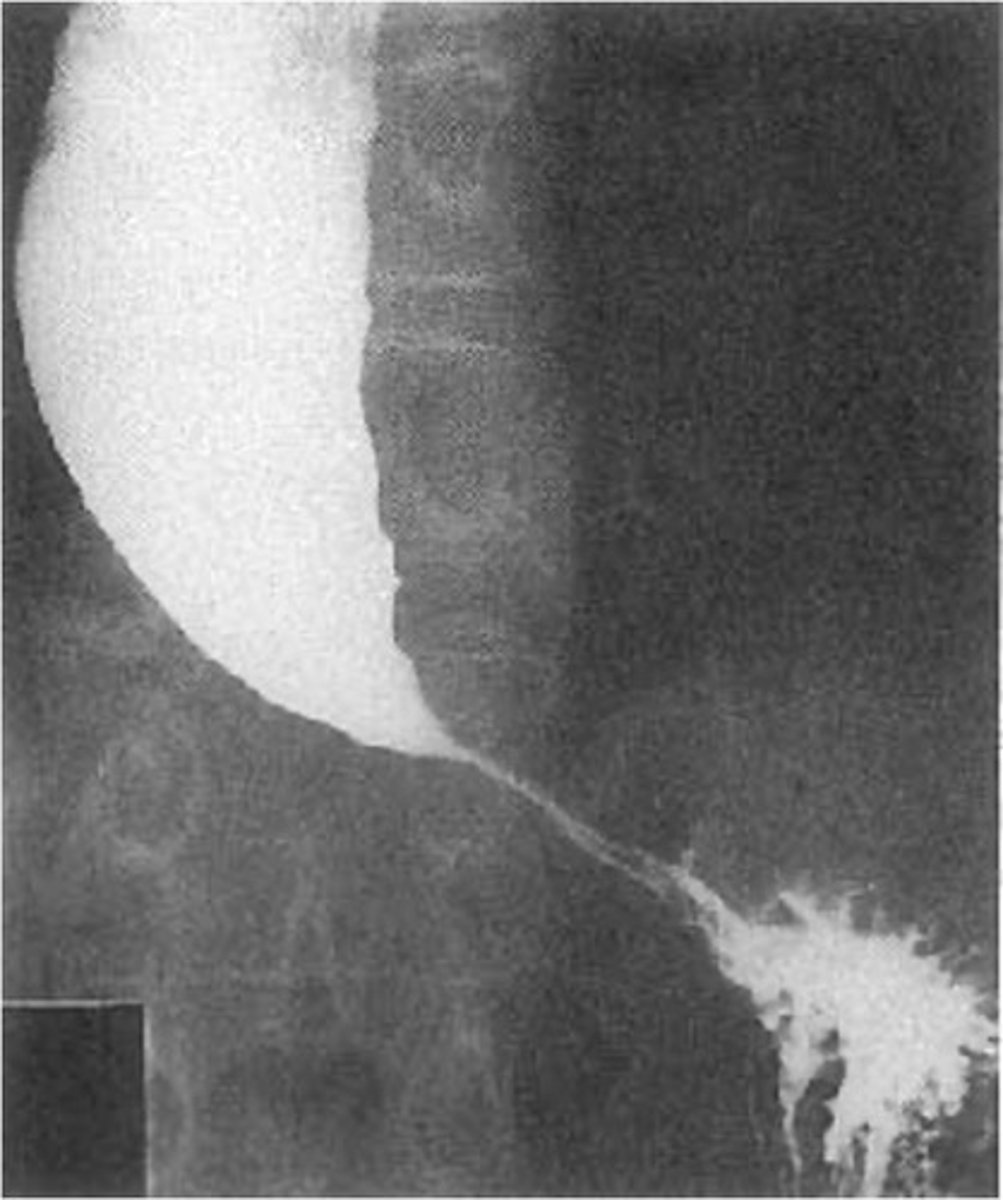

Esophageal cancer: ulcers and mass

Barretts esophagus